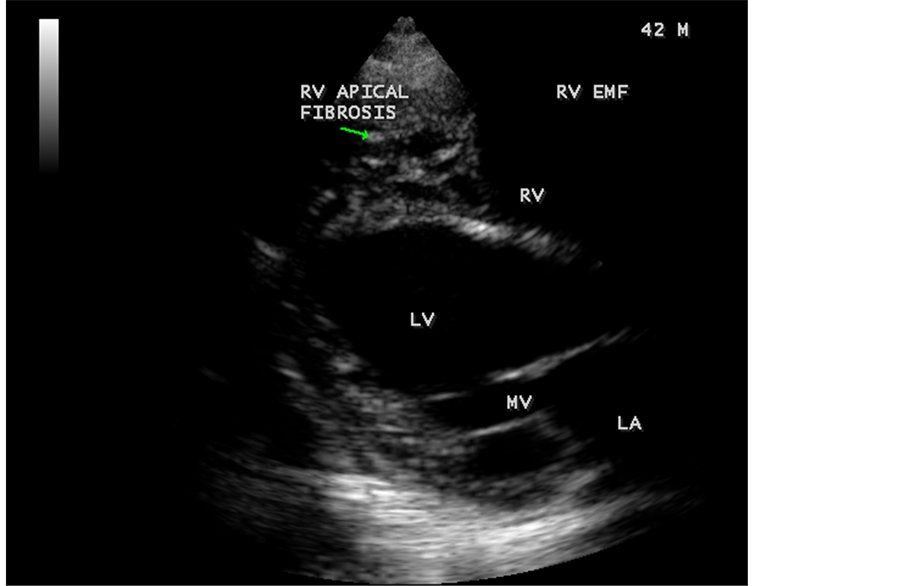

Figure 78. Parasternal long axis view showing RV apical fibrosis and aneurysmal LV (left ventricle) in a 42-year-old male.

Figure 79. Tilted apical view showing the AV valve regurgitation with smoke (spontaneous echo contrast) in both ventricles in EMF in a 42-year-old male.